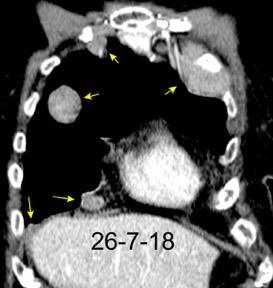

Pliegue axilar Normal

Rehúsa cirugía

2011. Acude por masa axilar

Linfoma NH de cél. B. Invasión Transtorácica.

Afectación axilar